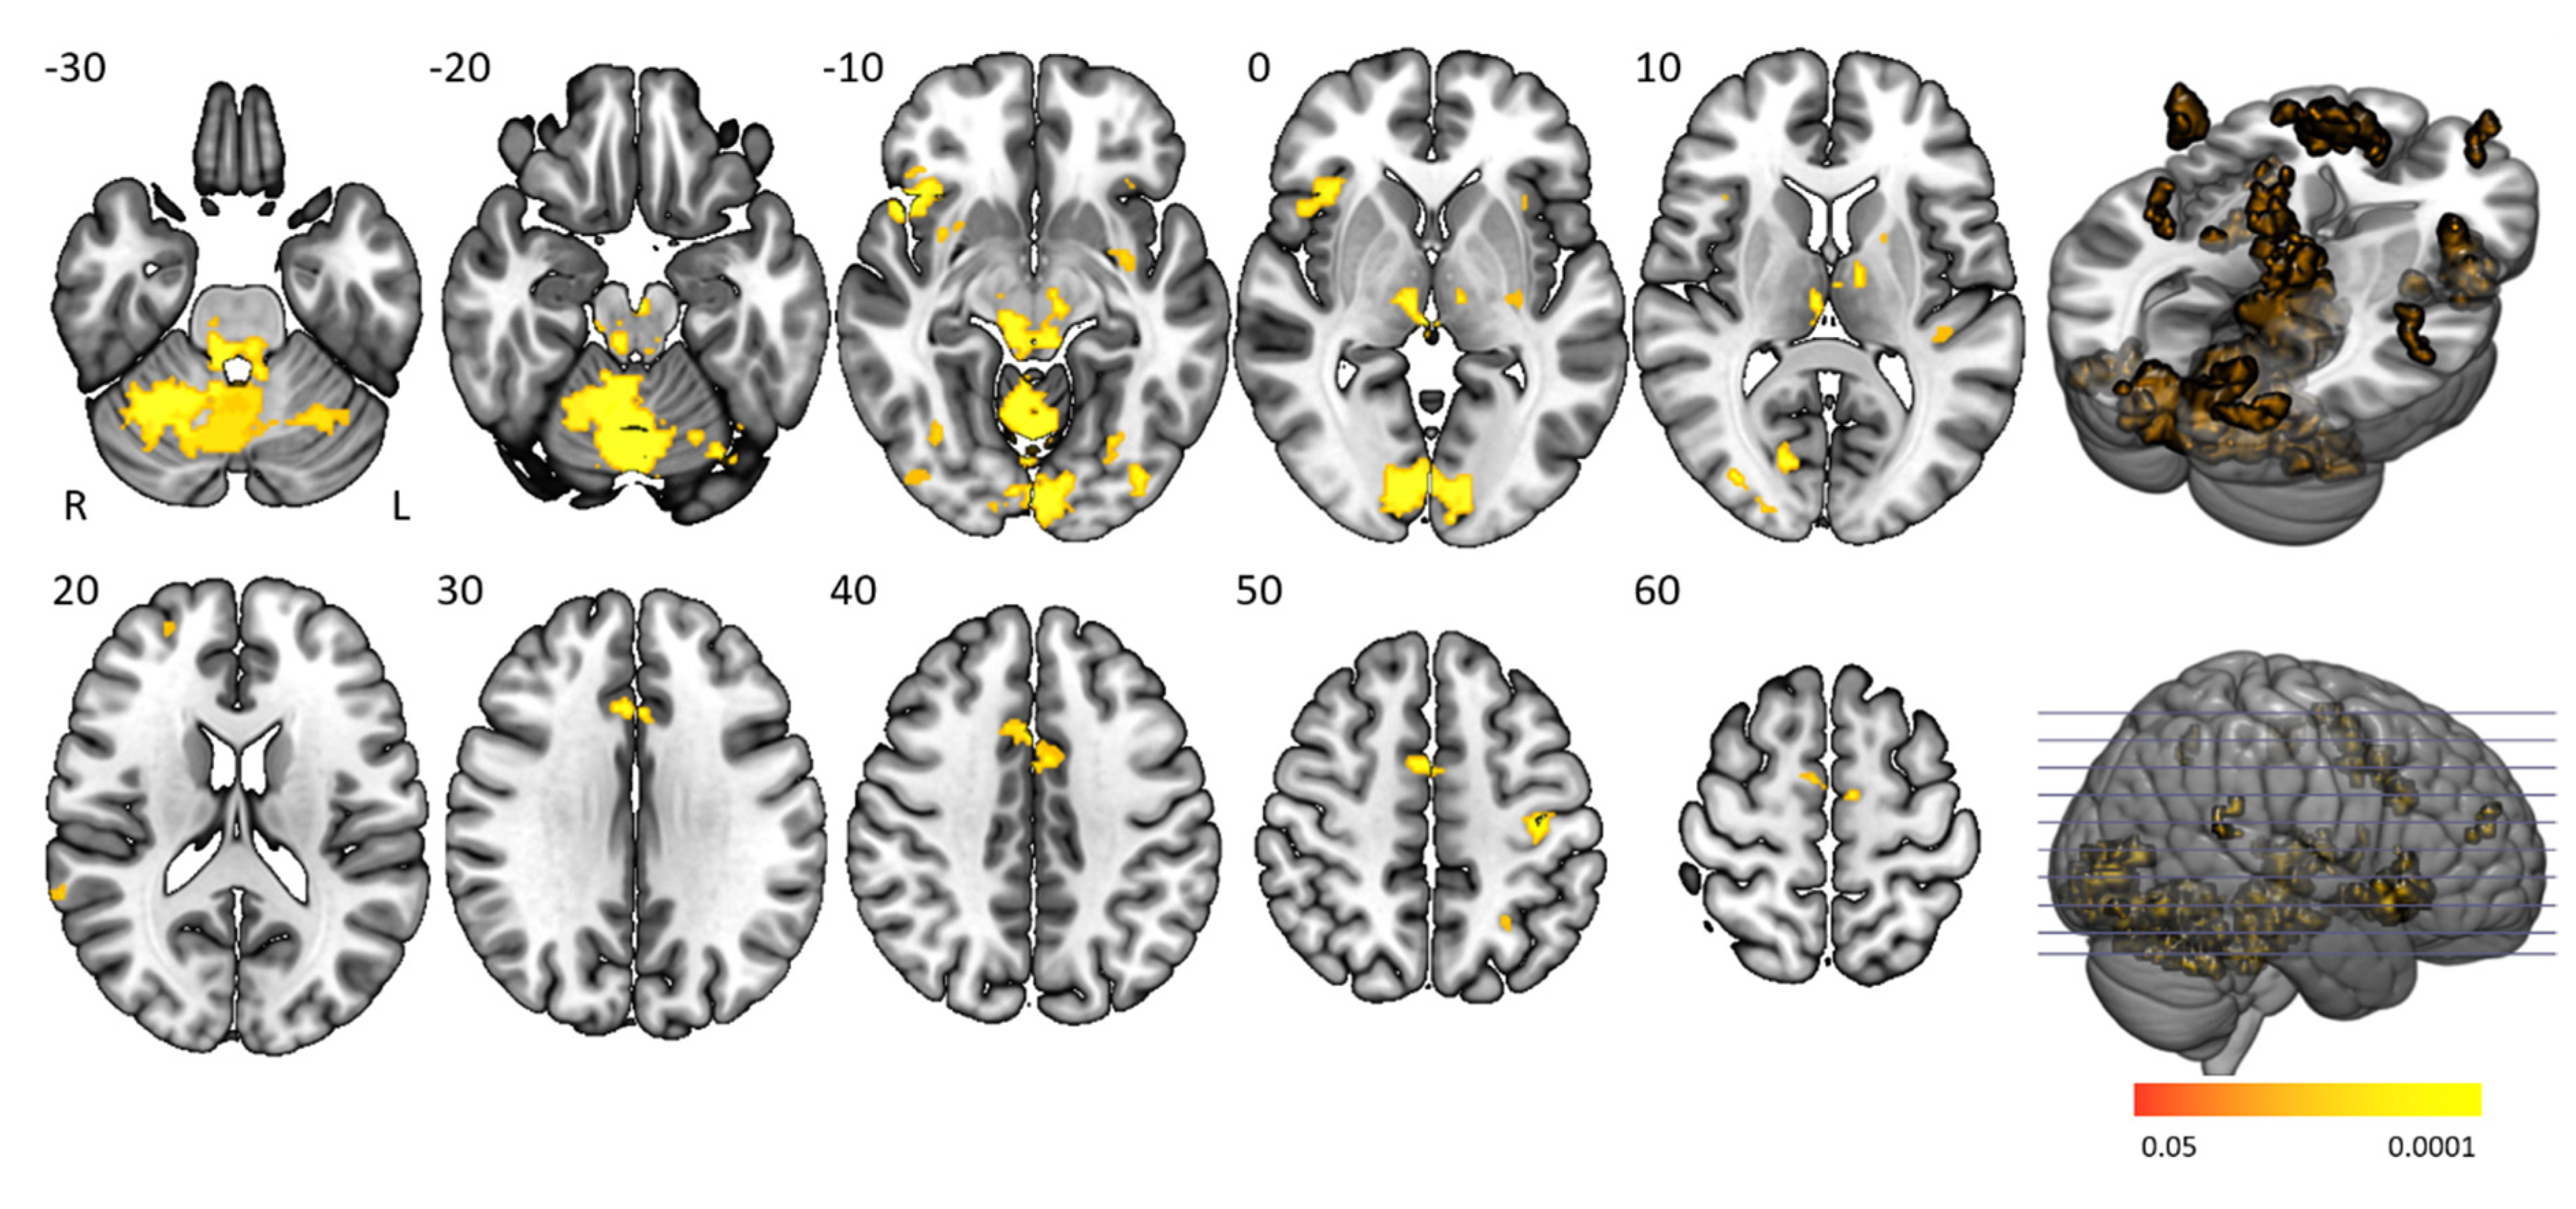

3.4. Time-On-Task Effects

Time-on-task analyses comparing BOLD signals in repetition 1 and 4 between participant groups yielded no significant activation differences. Time-on-task within blocks analyses demonstrated that people with narcolepsy type 1 had significantly less activation than controls in the “late half > early half” contrast combining the two difficulty levels. Post-hoc analyses showed that this effect was driven by the higher difficulty level, as shown in Figure 4 and Table 3. Significantly lower activation was found in people with narcolepsy type 1 in regions including the cingulo-opercular network (bilateral insula and operculum, left anterior cingulate cortex, right middle frontal gyrus, and thalamus), frontoparietal network (bilateral superior frontal gyrus, midcingulate cortex and right inferior frontal gyrus, and angular gyrus), (regulatory) motor areas, and visual regions. Other activated regions were the bilateral temporal lobe and inferior orbitofrontal gyrus and the right angular gyrus. The between-group differences were mainly driven by controls upregulating their neural efforts within higher difficulty blocks, whereas people with narcolepsy type 1 maintained stable activation over time. Decreased activation over time was only seen in those with narcolepsy type 1, in the visual cortex and cerebellum. No between-group time-on-task within blocks differences were seen in difficulty level 1.